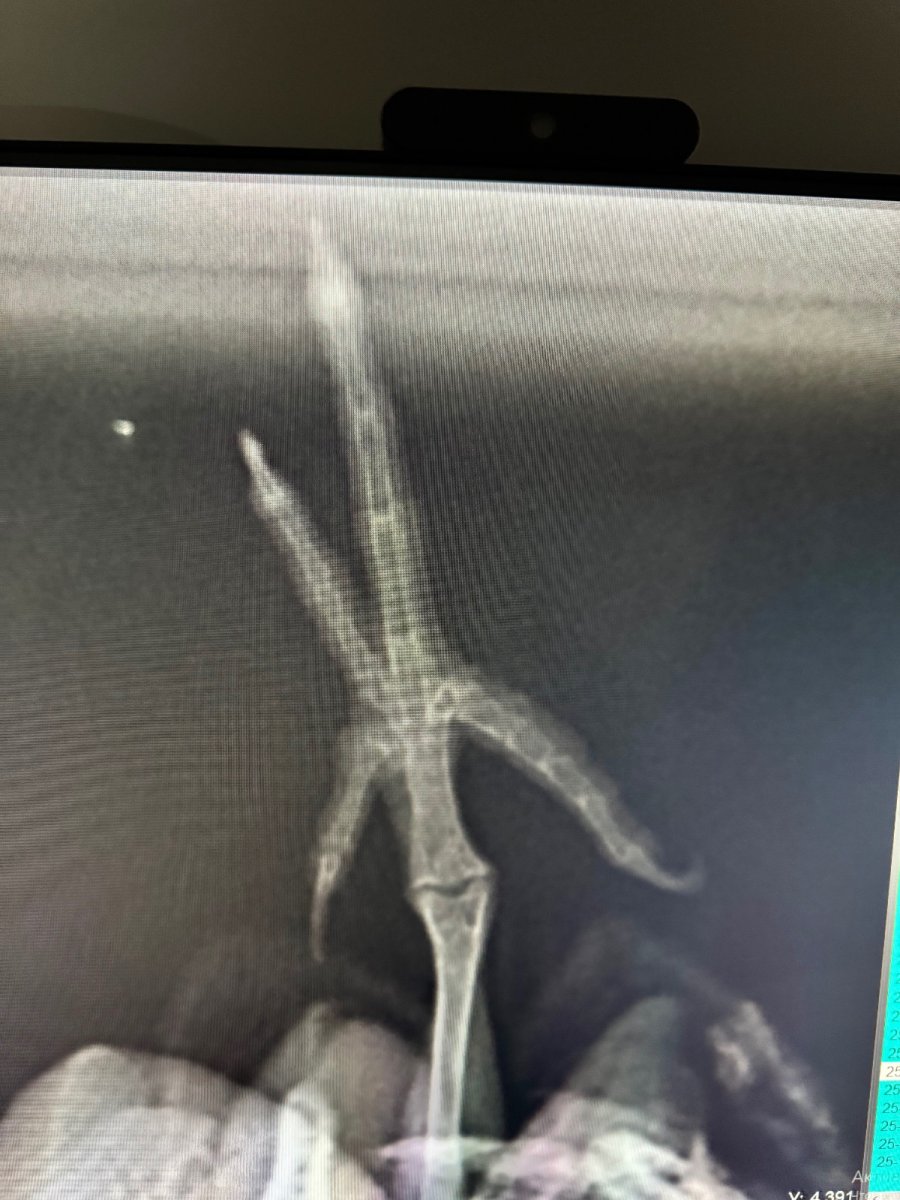

Здравствуйте. Корелла мальчик 16лет будет в феврале. Где то в квартире зацепился и сломал ноготь на длинном пальце, немного покровоточил, долго не вставал на лапку, повезла в ветеринарку, по рентгену сказали что у него вывих заднего пальчика. Прописали мелоксивет, кальция борглюконат и аквадетрим, все в клюв. Вес птички 90гр. Все в пропорциях 0.09, 0.05 и 0.03мл. Никогда ничем не болел, никогда ничего не употреблял. Знаю что у птиц слабые желудки и почки, не знаю реакции своего попугая на данные препараты. Боюсь чем либо пропаивать. Кушает хорошо, помет с виду отличный, только лапка беспокоит, болит уже больше недели, не напрягает ее, пальчики не сжимает, похрамывает и просто опирается на нее. Что посоветуете делать? Помогите пожалуйста.